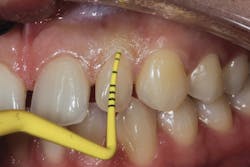

Because of this alveolar resorptive pattern after tooth extraction, bone grafting the extraction socket after tooth extraction procedures has become a solution that attempts to limit the amount of hard- and soft-tissue loss. There are many systematic reviews in the literature that compare the results of residual ridge dimension following tooth extraction after the use of a bone graft (with or without a membrane) versus extraction alone without grafting.7

Indications for bone grafting extraction sites include:

• site development to increase hard and soft tissue for pontic sites in fixed bridge prosthetics (figures 9–14);• correcting bone defects impinging upon anatomical structures after tooth extraction, such as oroantral communication (figure 18); and

• preserving tissue structure for subsequent dental implant therapy.Decision matrix